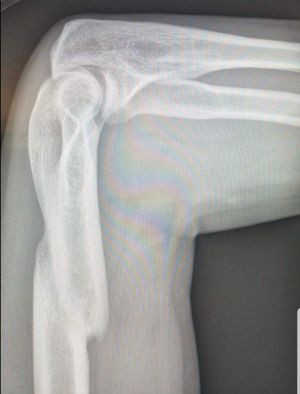

Diagnosis and recommended treatment?

Fracture of the Humerus. Injury to the radial nerve.

fracture mid shaft of humerus treatment is pop cast and arm holder